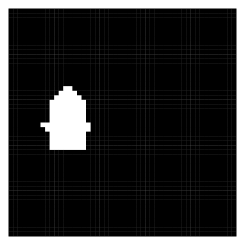

Here we are interested in recovering a target structure in a two-dimensional image using atlases. We simulate a 40 40 grid, displayed in Figure 2. Suppose that each of the atlas segmentations perform well, each being only slightly offset from the truth. The atlases are also displayed in Figure 2.

To compare results of our procedure with and without covariates, we find the signed distance label (SDL) transforms for each atlas (Iglesias et al., 2012). An SDL transform for a binary image assigns to each pixel a number corresponding to its distance from the nearest edge in an image, where an edge is indicated by a zero adjacent to a one. The sign of the distance corresponds to whether or not the pixel is inside or outside an identified structure; e.g., a pixel has negative distance if it is inside the structure, positive distance if it is outside, and zero if it is on the boundary. We consider the sum of the signed distance label transform maps as a possible covariate. In this case, the dimension of the predictor space with and without the covariate included is and , respectively. In the former case, our CMP prior is induced by supposing a priori that a voxel with a large negative signed distance label has probability 0.9 of being in the structure, and probability 0.10 if its signed distance label is large positive. With no predictors at all, we induce the prior on by supposing there is a 50% chance that a borderline voxel (signed distance label = 0) is truly part of the structure. Further discussion of prior elicitation for the numerical experiments, as well as MCMC implementation, is in the online Supplementary Material.